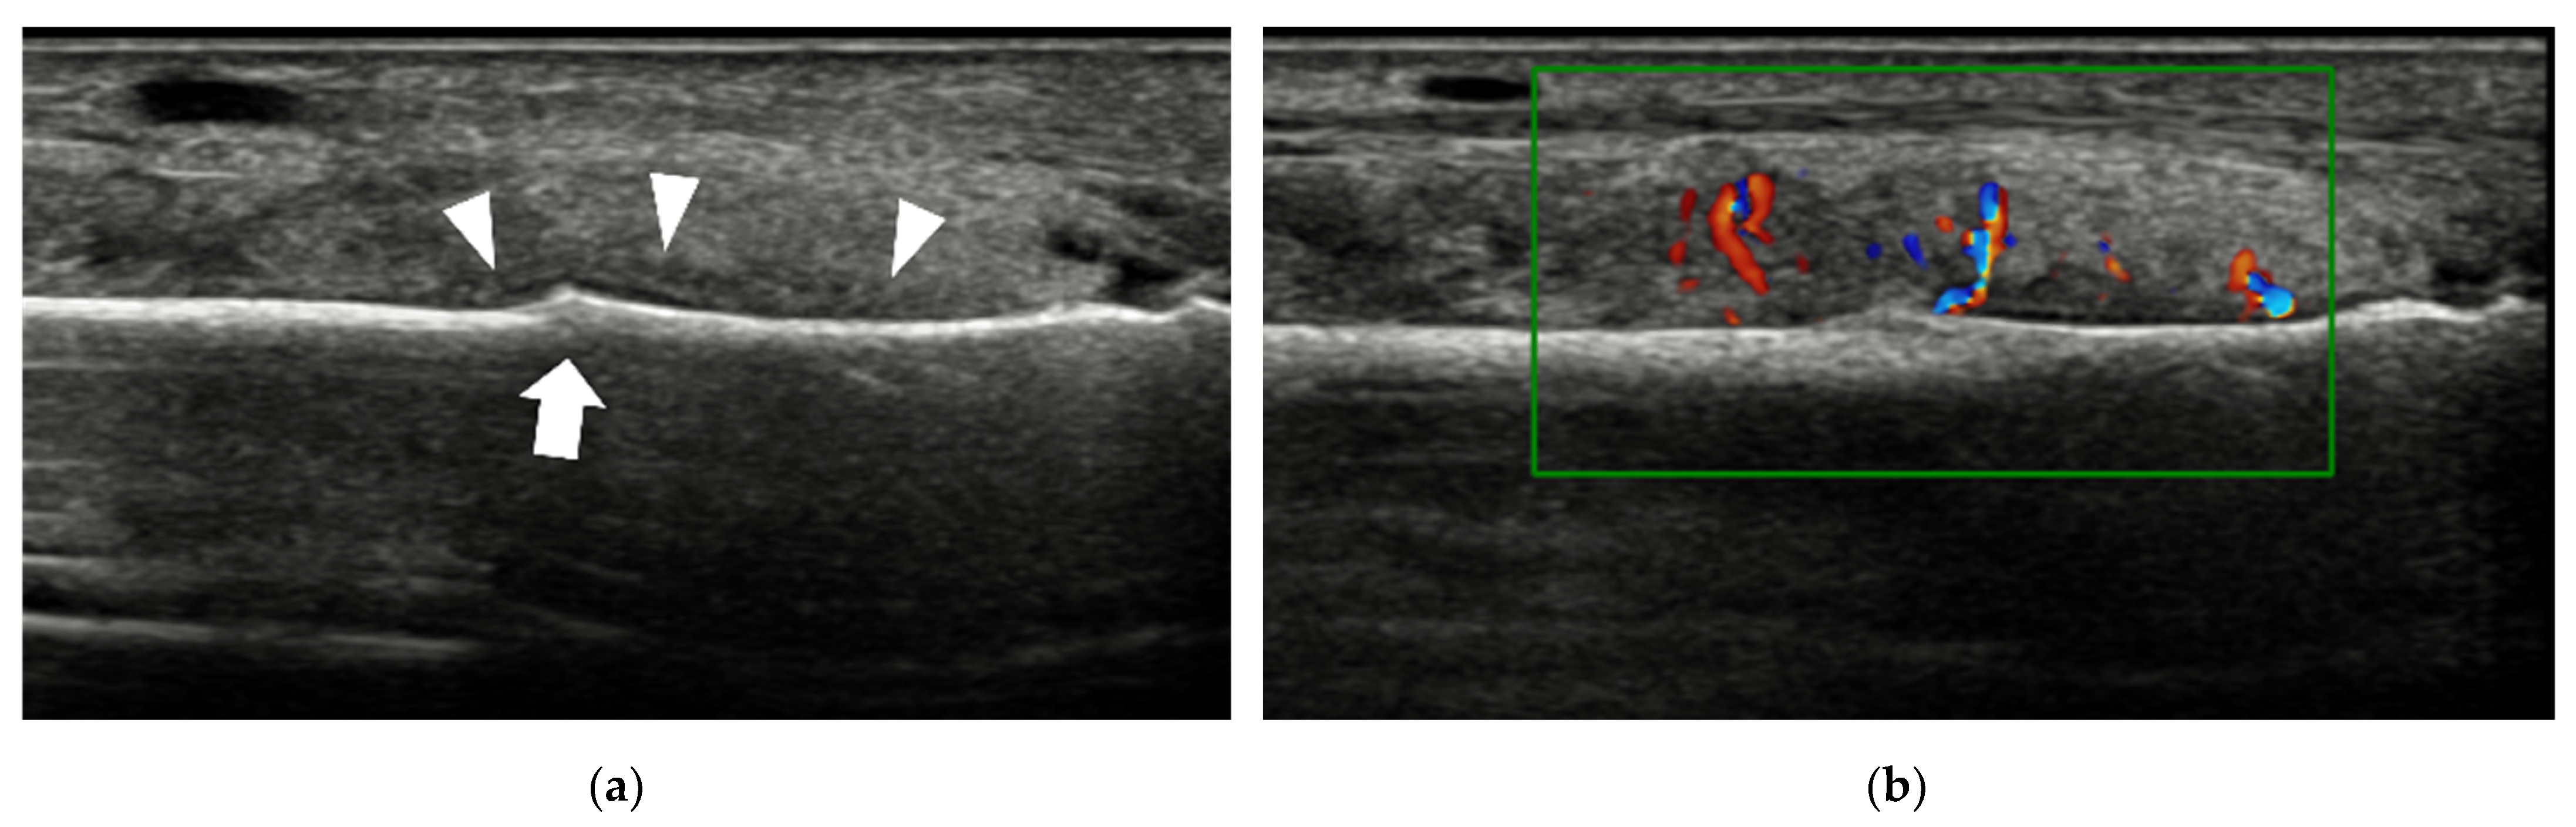

4.1.1. Plantar Plate Tear

| Plantar plate tear | 2nd MTP joint | discrete anechoic cleft or area of heterogeneous echotexture in the plantar plate |